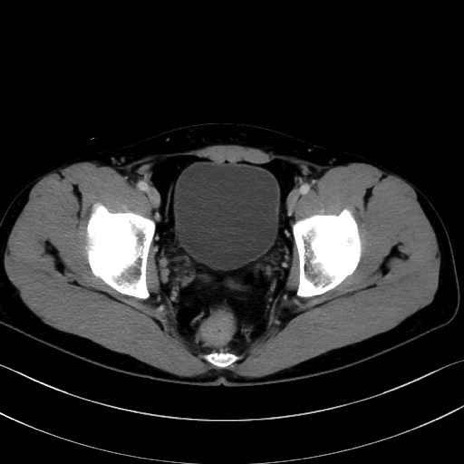

大殿筋 (Gluteus maximus)

中殿筋 (Gluteus medius)

小殿筋 (Gluteus minimus)

梨状筋 (Piriformis)

内閉鎖筋 (Obturator internus)